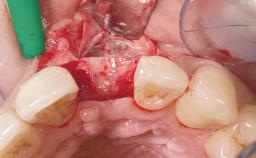

Immediate Placement of an Implant in a Maxillary Left Central Incisor Site

Soft Tissue Grafting Simultaneous

Soft Tissue Contour and Volume Slightly compromised